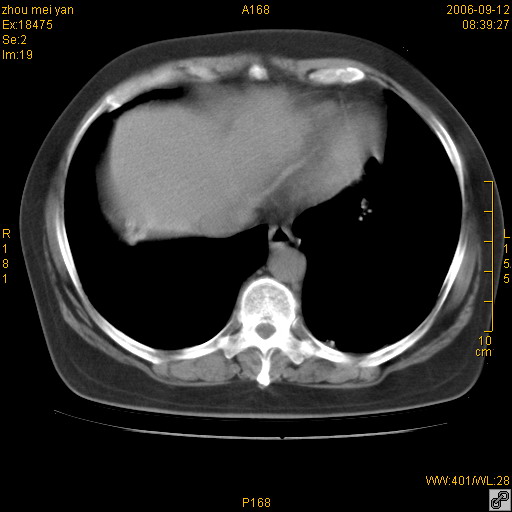

患者、女、55岁。因心率失常住院检查ct发现胸部多发结节。腹部b超肝、胆、胰、脾、肾、子宫附件未见异常。无结核病史,无粉尘接触史。请大家来会诊。谢谢!

病变位于胸膜,多发结节,边界清楚,内见小结节状钙化。其它未见异常。

双侧胸膜多发结节,形态不规则,边缘较清楚,每一个结节中心似乎都有钙化点的特征,与胸膜广基相切。临床无结核病史,无粉尘接触史。

胸膜间皮瘤可能性大。在气管隆突前可见一肿大淋巴结影。

影像表现十分有特点:双侧肋胸膜及膈胸膜广泛散在分布大小在2至6mm左右,较大病灶中心可见钙化。

感染性肉芽肿,双侧膈底胸膜见多个结节灶,内见斑点状钙化,有否疫水接触史

双侧肋胸膜及膈胸膜广泛散在分布大小不等结节影,较大病灶中心可见钙化。